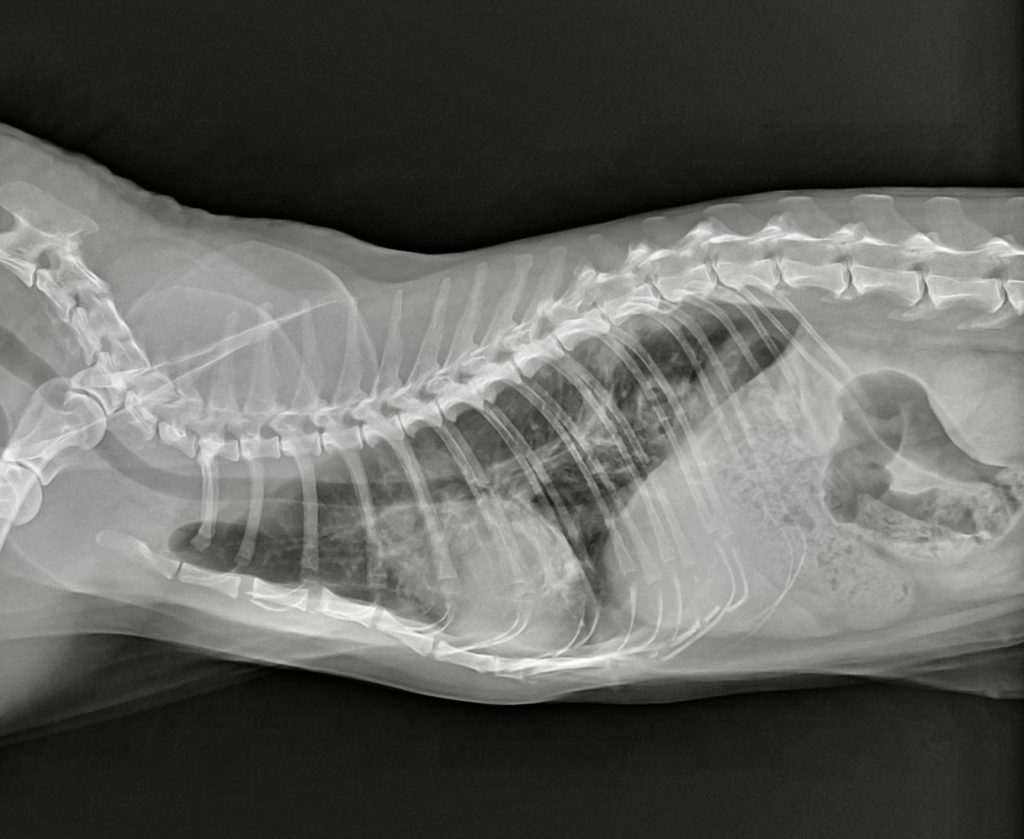

腫瘍や炎症の可能性を考えました。特に足や指の腫瘍も考えましたが、左右の前足で同時に症状が出ていることに違和感を感じました。足や指の腫瘍なら、通常は片方の足だけ出ることが多いです。そこで、ある疾患が鑑別疾患に挙がり、肺のレントゲンを撮影しました。

この結果からやはり鑑別疾患に挙げていた肺指(はいゆび)症候群と診断しました。肺指症候群とは、肺癌が四肢の指先に転移する猫ちゃん特有の病態です。

また、診断時には肺癌が指以外にも全身転移していることがほとんどで、予後は極めて悪く、余命は1-2ヵ月程と言われています。肺癌でも末期的な状態なので積極的な治療は難しく、今回は痛みを取ることが中心の緩和治療を実施することになりました。